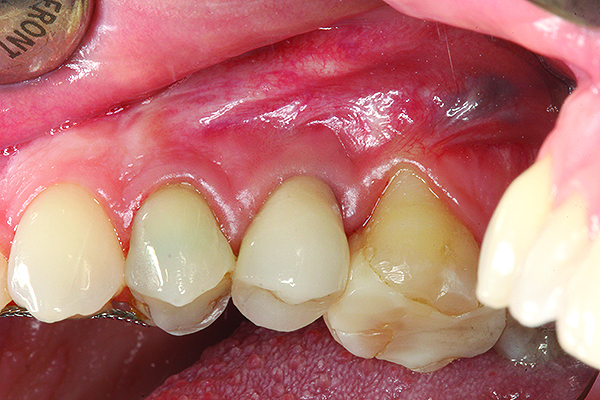

A implant restoration with a buccal dehiscence of bone and soft tissue caused by poor implant positioning, lack of keratinized tissue prior to implant placement, and soft tissue recession post implant restoration.

Figure 8

The same implant in Fig 8, 7 years following treatment, which included two autogenous connective tissue grafts and a bone augmentation surgery with a combined allograft and xenograft mixed with two biologics.

Figure 9

The implant of the patient shown in Figure 8 demonstrated all three of the red flag situations: it was placed too far buccally, had inadequate bone and soft tissue at the time of implant placement, and lost bone and soft tissue post implant placement. Correcting this required increased time, cost, and surgeries (Figure 9).